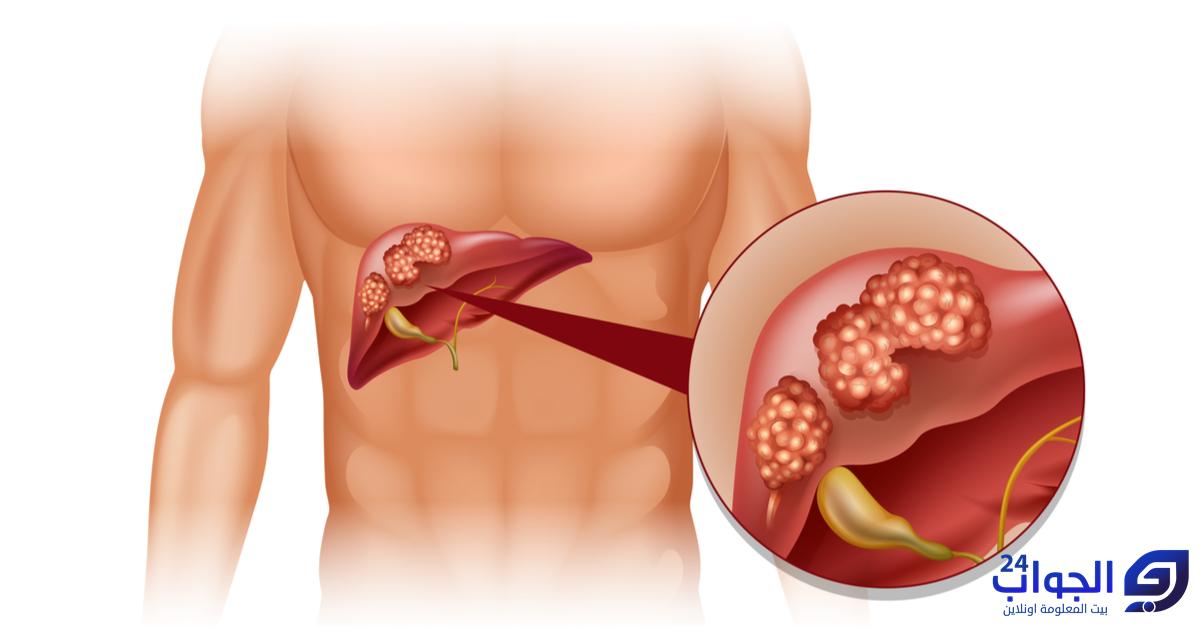

سرطان الكبد هو نمو غير طبيعي للخلايا في أنسجة الكبد، الذي يعد واحدًا من أكبر الأعضاء الداخلية في جسم الإنسان. يمكن أن يتكون سرطان الكبد من خلايا الكبد السليمة أو ينشأ من انتشار سرطان من مناطق أخرى من الجسم إلى الكبد.

- سرطان الكبد الأولي: يبدأ هذا النوع من السرطان في خلايا الكبد نفسها. وأكثر أنواع سرطان الكبد الأولية شيوعًا هو سرطان خلايا الكبد، والذي ينشأ من خلايا الكبد البطانية.

- الأورام الثانوية: هذه الأورام تنشأ عادةً عندما ينتشر سرطان من مواقع أخرى في الجسم إلى الكبد، وتُعرف أيضًا بالأورام الناتجة عن الانتشار فعلى سبيل المثال، سرطان الثدي أو سرطان القولون قد ينتشر إلى الكبد.